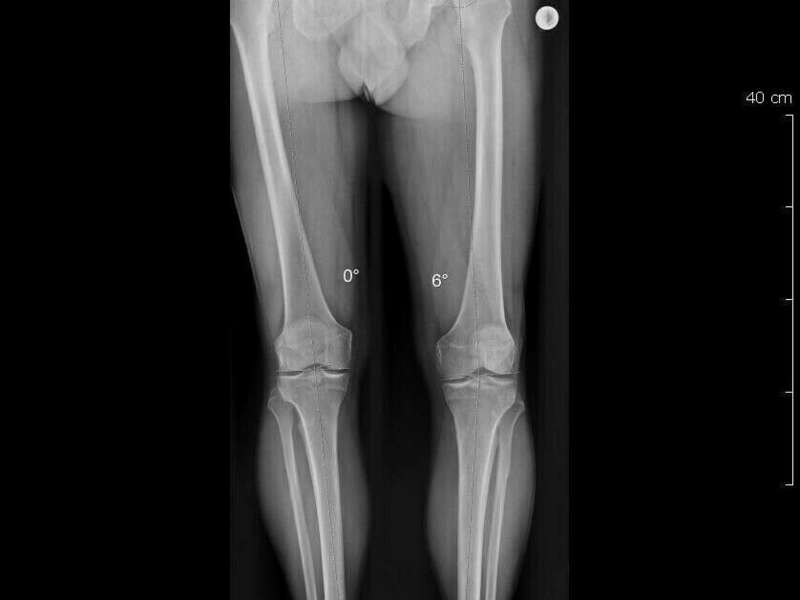

- Les anomalies anatomiques plus ou moins constitutionnelles : inégalité de longueur de membre, dysplasie fémoro-acétabulaire, luxation de hanche, les fracture de hanche, les lésions ligamentaires.